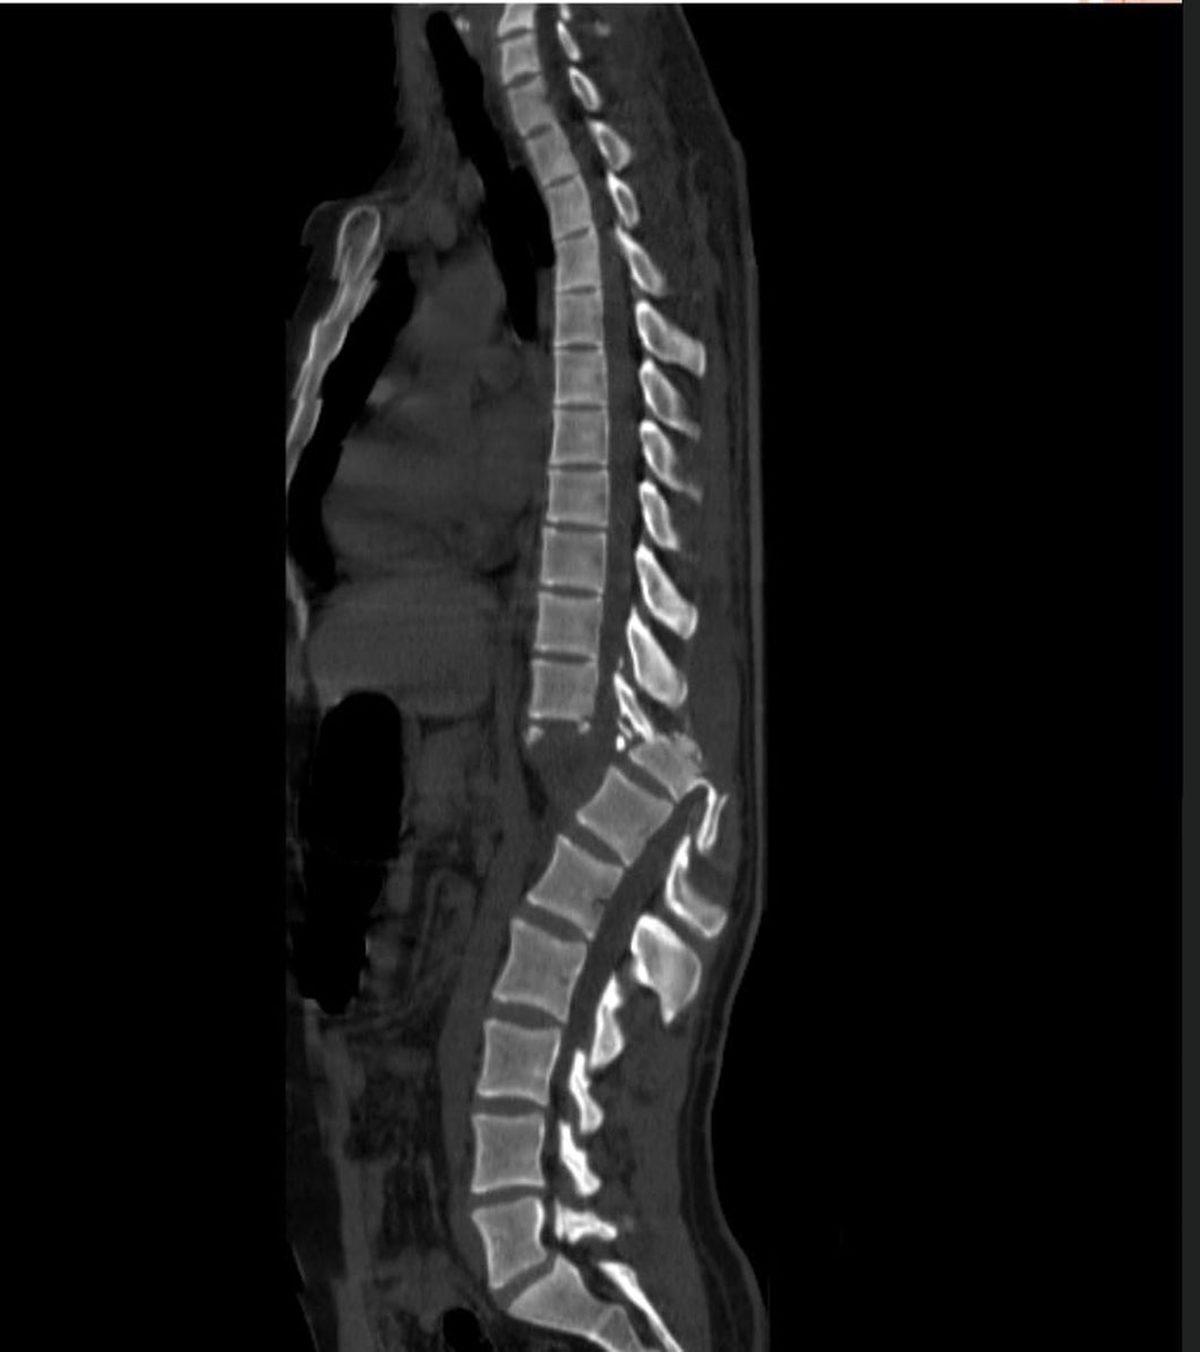

- Skolyoz rahatsızlığı olan biri.

Normalde böyle görünüyor: